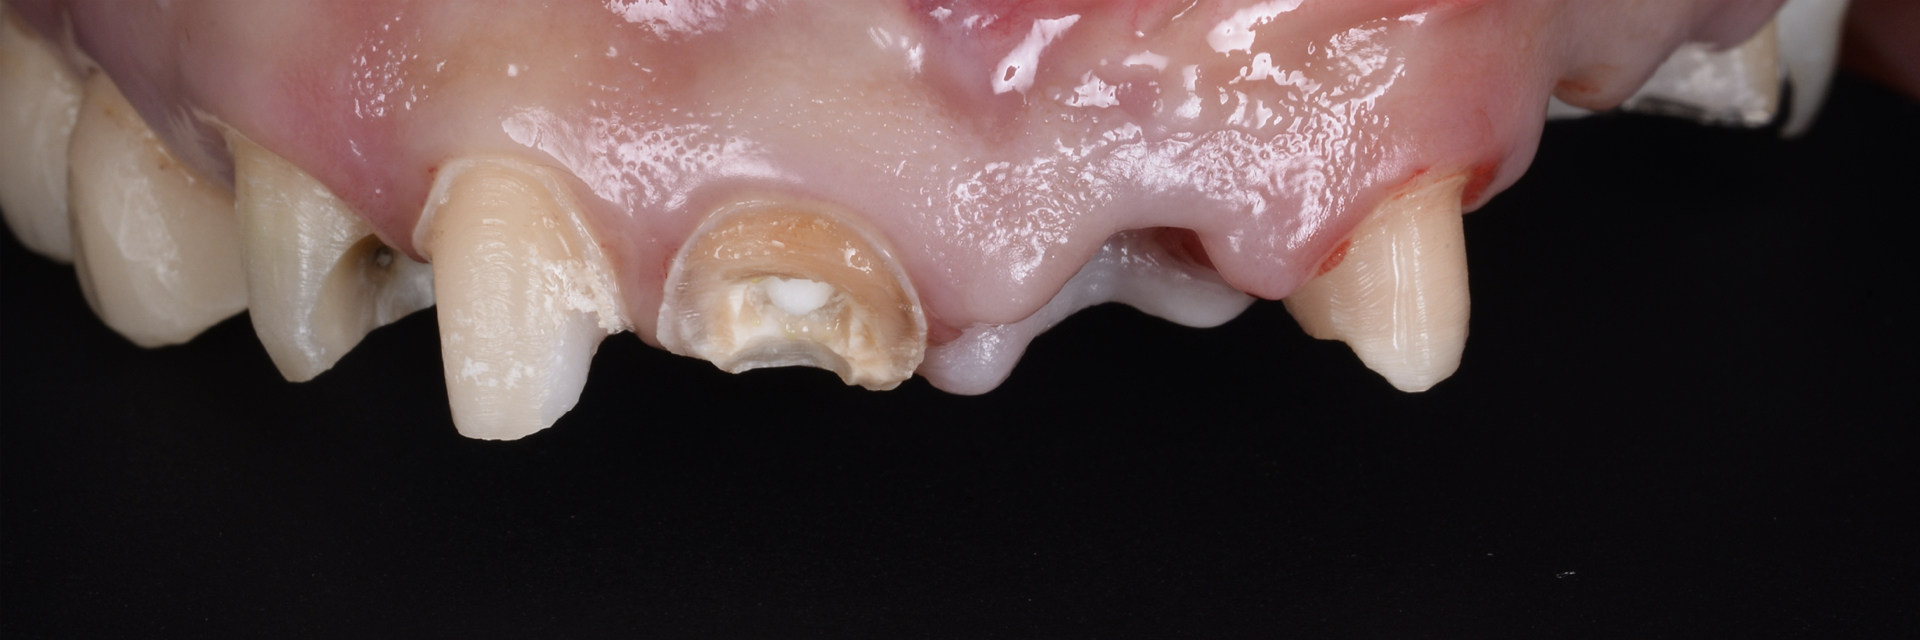

右下奥歯に瘻孔を認め、歯肉の腫脹を認めた。レントゲンで周囲骨が高度に吸収していた。

治療前

治療前